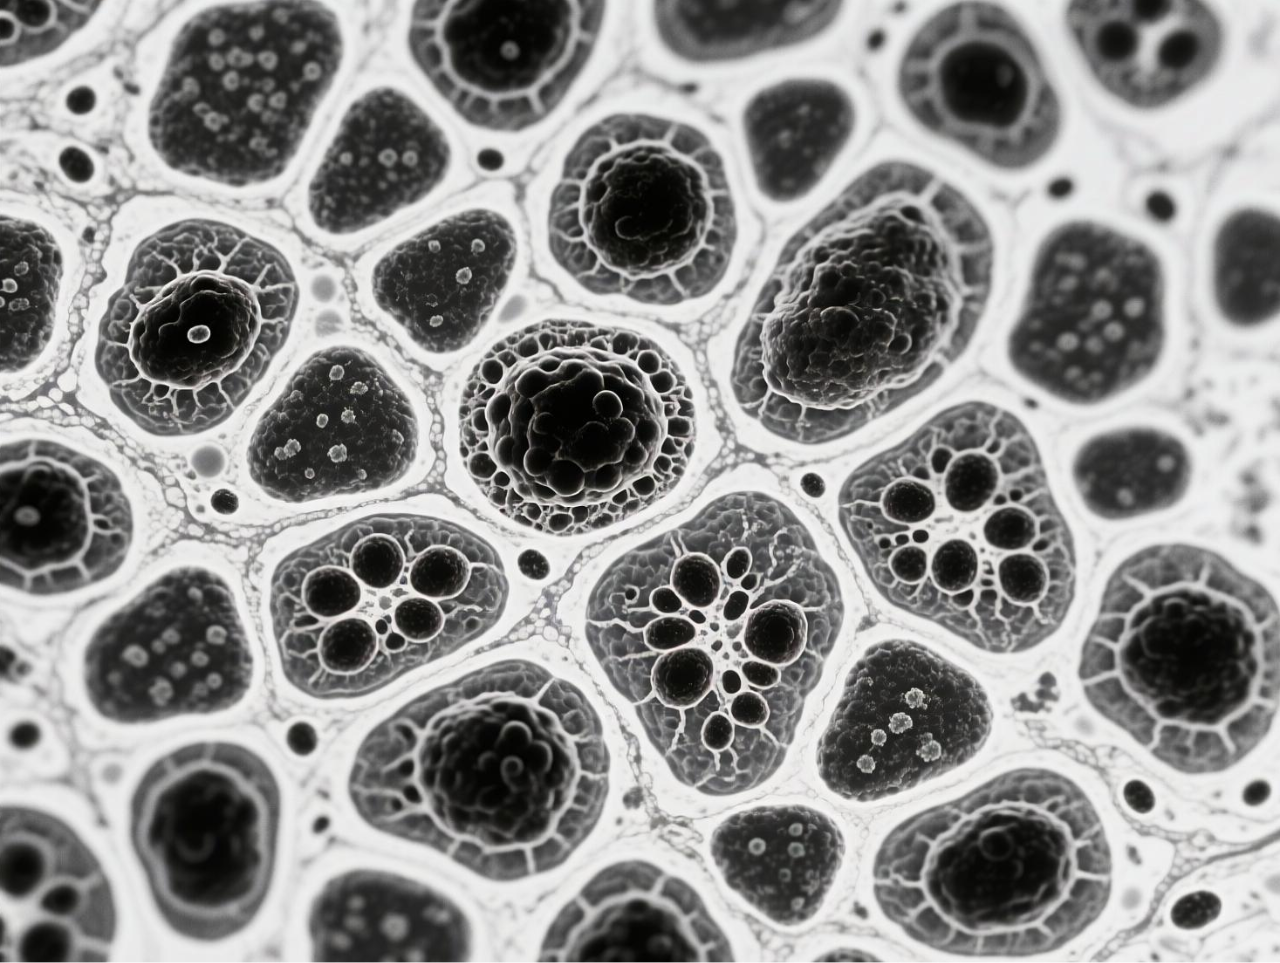

圖 BCG-MBs的制備與表征

臺(tái)式掃描電鏡在本研究中發(fā)揮了關(guān)鍵的表征作用,為微氣泡系統(tǒng)的結(jié)構(gòu)驗(yàn)證提供了直觀而精確的證據(jù)。研究團(tuán)隊(duì)使用澤攸科技ZEM18臺(tái)式掃描電鏡對(duì)凍干后的BCG-MBs進(jìn)行金濺射鍍膜處理后,在不同放大倍數(shù)下觀察其表面形態(tài),清晰地展示了微氣泡規(guī)則的球形結(jié)構(gòu)以及BCG在微氣泡表面的不規(guī)則分布狀態(tài)。這一表征不僅確認(rèn)了微氣泡制備工藝的成功,還直觀揭示了BCG在微氣泡中的物理分布特征,為理解藥物釋放機(jī)制提供了結(jié)構(gòu)基礎(chǔ)。掃描電鏡圖像作為重要的形態(tài)學(xué)證據(jù),有力支持了后續(xù)對(duì)微氣泡浮力特性、藥物釋放行為及生物效應(yīng)的分析,是連接材料設(shè)計(jì)與功能驗(yàn)證的關(guān)鍵環(huán)節(jié)。